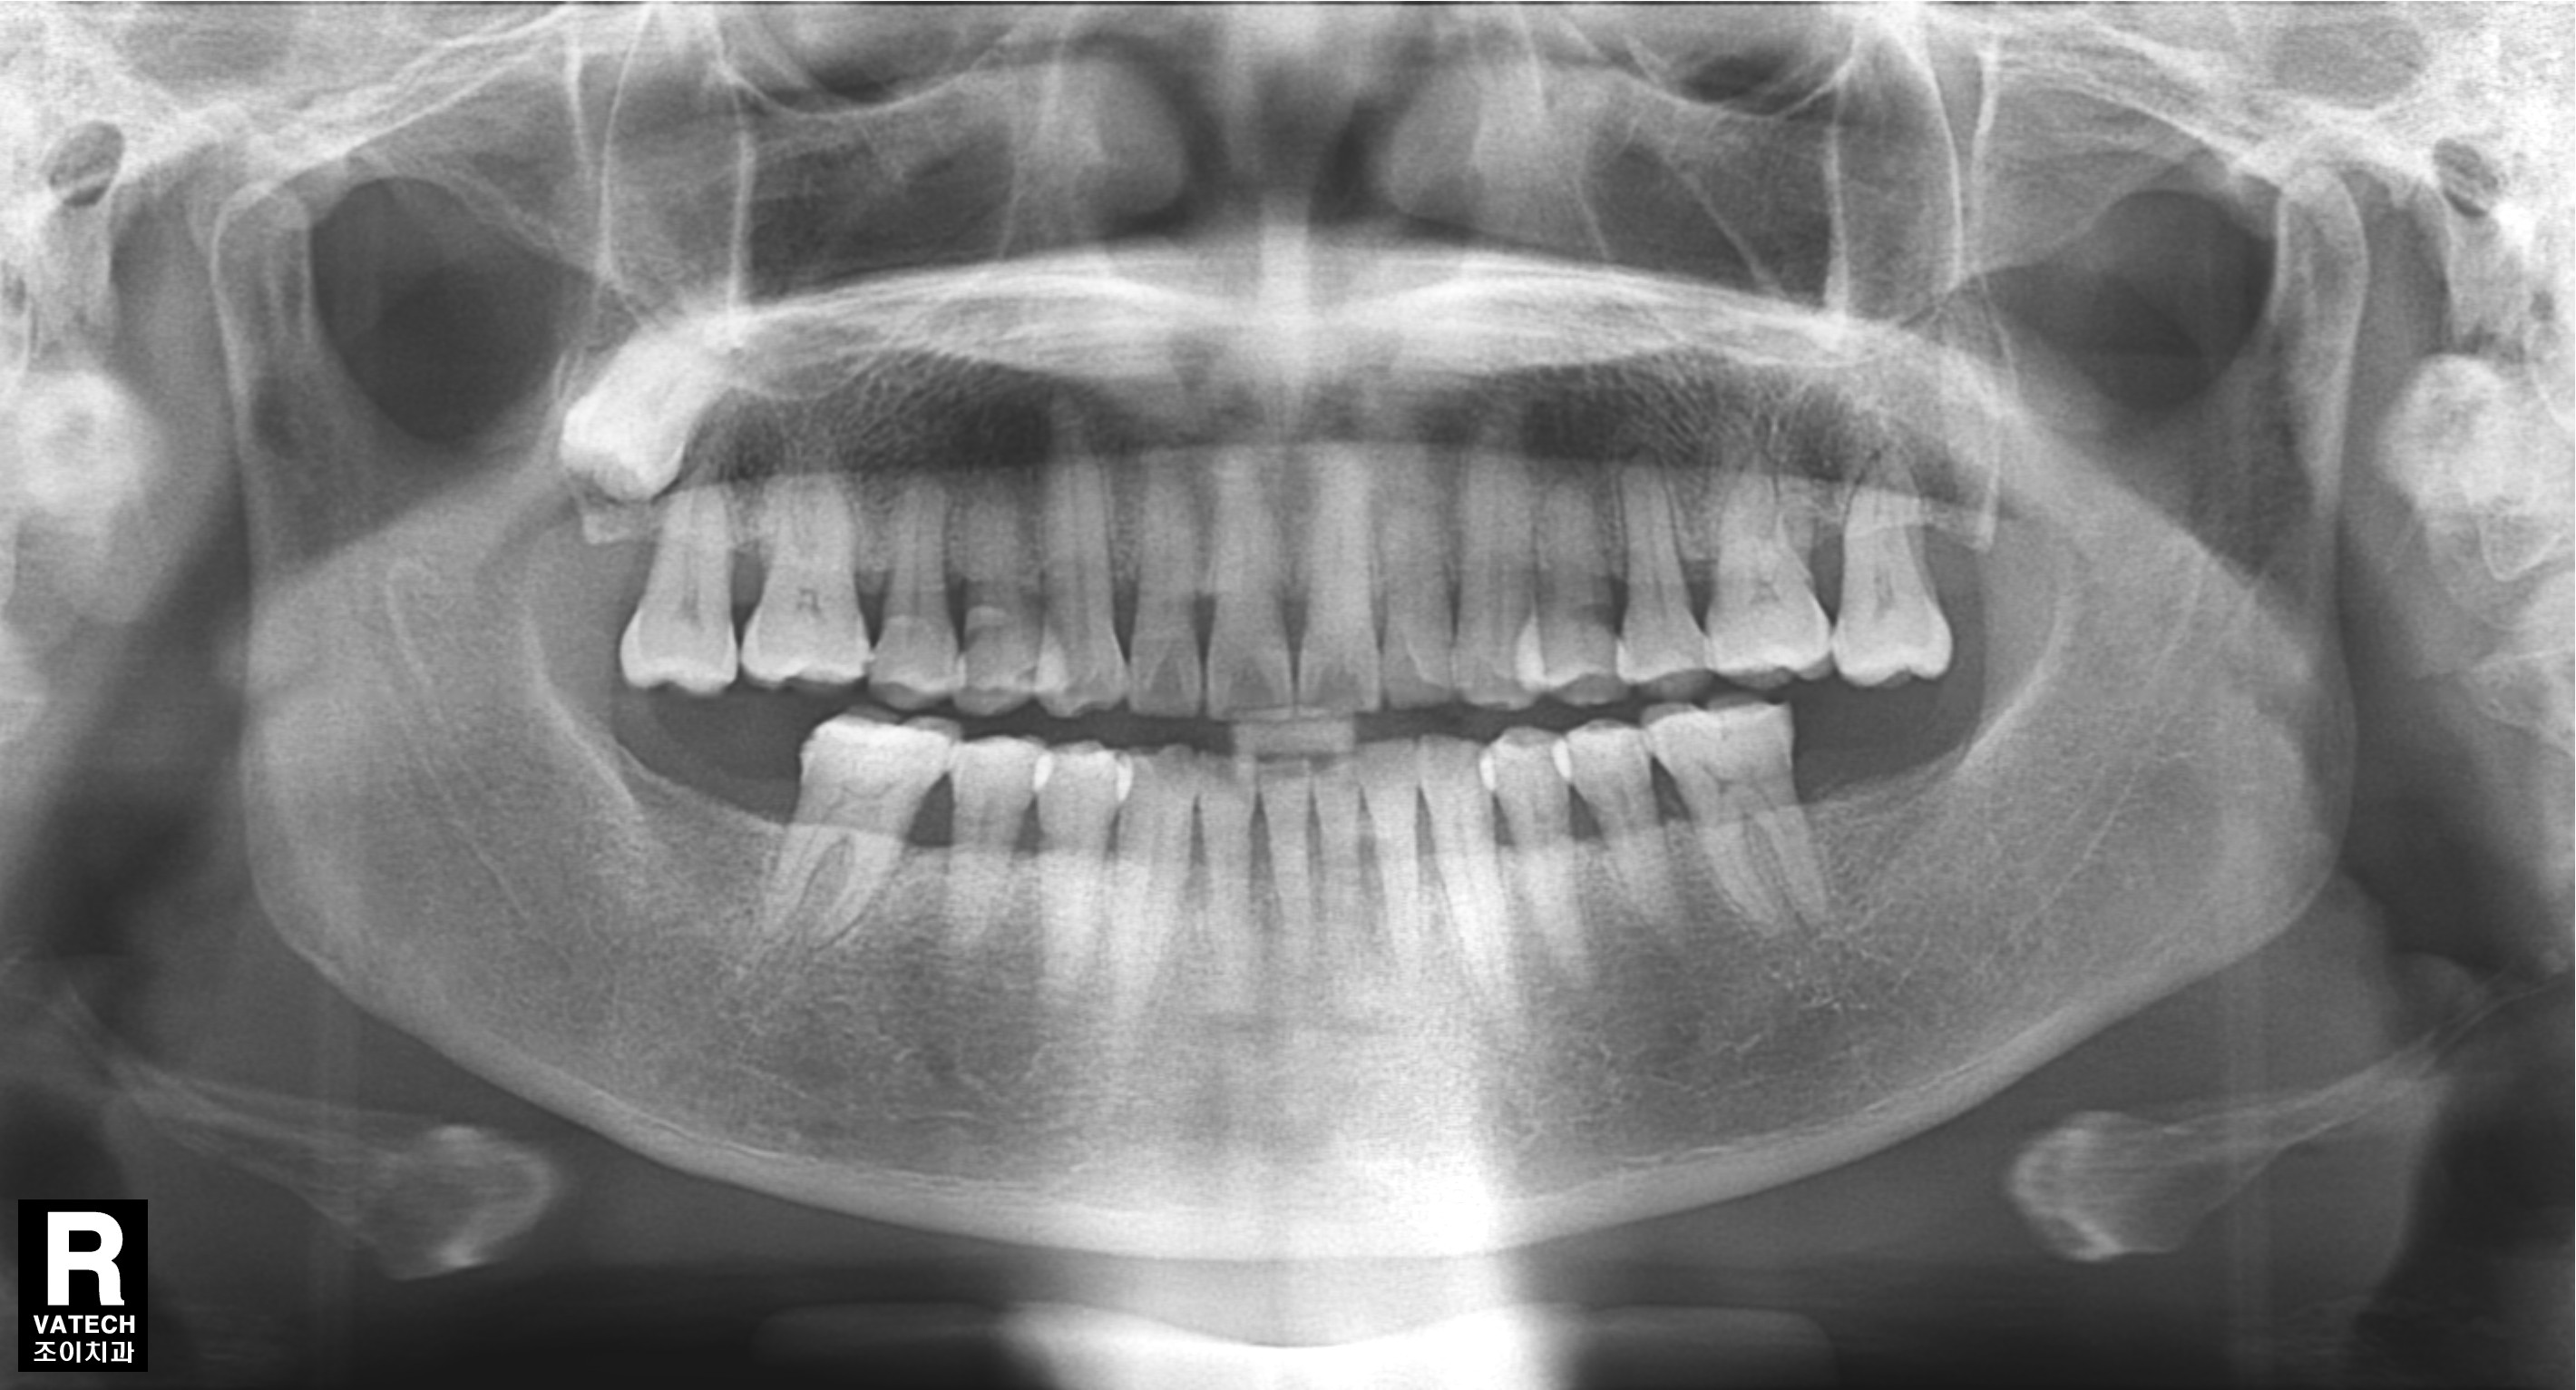

[임플란트] 제목 : 하악구치부 임플란트

이가 빠지면 반대편 이가 정출되어 공간이 좁아지게 됩니다.

이런 경우에 반대편 이도 치료를 하여 공간을 만들어 준 후 임플란트를 식립하여야 합니다.